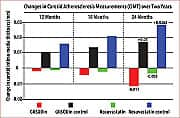

About a year and a half after commencing daily supplementation with GliSODin®, measurable decreases in subjects’ IMT were detected. Approximately two years after starting GliSODin® supplementation, decreases in IMT values became statistically significant. In dramatic contrast, control subjects not receiving GliSODin® experienced increased IMT values over the same period.21 There were no reported side effects in either group. This remarkable study demonstrated that reversal of atherosclerosis in adults with multiple risk factors for future cardiovascular disease is possible through a combination of healthy diet and daily intake of GliSODin® (orally bioavailable superoxide dismutase). These findings were confirmed by monitoring of clinical and biological health parameters, and measurements of carotid IMT. The GliSODin® regimen, “improves, significantly, the anti-oxidant status,” noted investigators, “and diminishes, remarkably, carotid artery IMT.”21 It should be noted that these findings echo those of other researchers, who, in previous and subsequent studies, have convincingly demonstrated GliSODin®’s ability to reduce oxidative damage in human volunteers and animal models.25-27 Pomegranate Fights Oxidative Damage, Reverses AtherosclerosisScientists have recently shown that pomegranate juice offers cardiac health benefits that complement those of GliSODin®. In the past seven years alone, the amount of published research on pomegranate has increased seven-fold over all preceding years in the medical and scientific literature.40 That’s almost certainly because each new study underscores the potential of this fruit to fight cancer and to combat oxidative stress. The latter is of particular importance for atherosclerosis prevention.

In 2004, researchers published the findings of a three-year study on the daily consumption of pomegranate juice (50 mL, or 1.7 ounces) by patients with advanced atherosclerosis.41 These patients were diagnosed with carotid artery stenosis; a serious condition in which the carotid arteries, responsible for supplying blood to the brain, become noticeably narrowed by buildup of atherosclerotic plaques. Such patients are at increased risk of suffering strokes or other “cerebrovascular accidents”. In this study, common carotid IMT increased by 9% within one year in the non-supplemented control group. Remarkably, patients drinking pomegranate juice experienced a whopping 35% reduction in the IMT score and a 44% improvement in carotid artery blood flow over the same period. Investigators also documented a 21% reduction in systolic blood pressure among the pomegranate juice drinkers. Serum total antioxidant status was increased by an extraordinary 130% after one year of pomegranate supplementation. Additionally, the scientists monitored the status of an enzyme that may protect against the development of atherosclerotic plaque by protecting LDL against oxidative modification. Pomegranate drinkers’ levels of this beneficial enzyme increased by 83% after just one year. “For all studied parameters, the maximal effects were observed after one year of consumption,” wrote the researchers.41